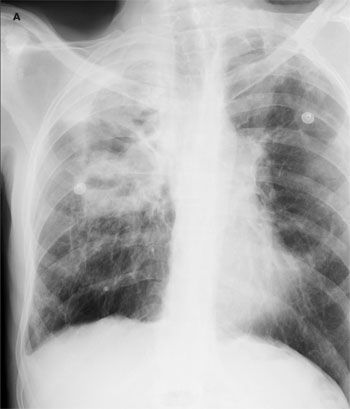

A 43-year-old white man presented to the emergency department with dyspnea, abdominal bloating, fever with chills, night sweats, decreased oral intake, and myalgia of 1 week's duration. He was found to have heart failure caused by systolic dysfunction. Viral myocarditis was the presumptive diagnosis after investigation for other causes.